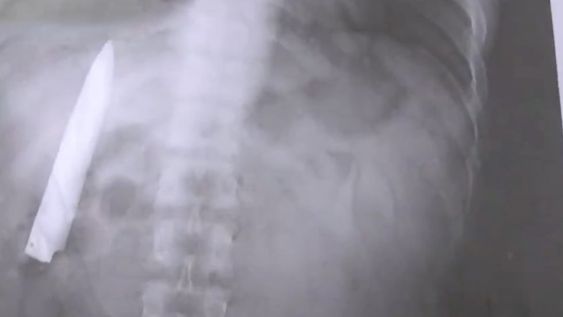

Un hombre filipino de 25 años se realizó algunas pruebas médicas y descubrió que lleva un cuchillo en su interior. Foto: Captura de Video

Sufría de dolores en el pecho, se hizo una radiografía y descubrió que tenía un cuchillo clavado